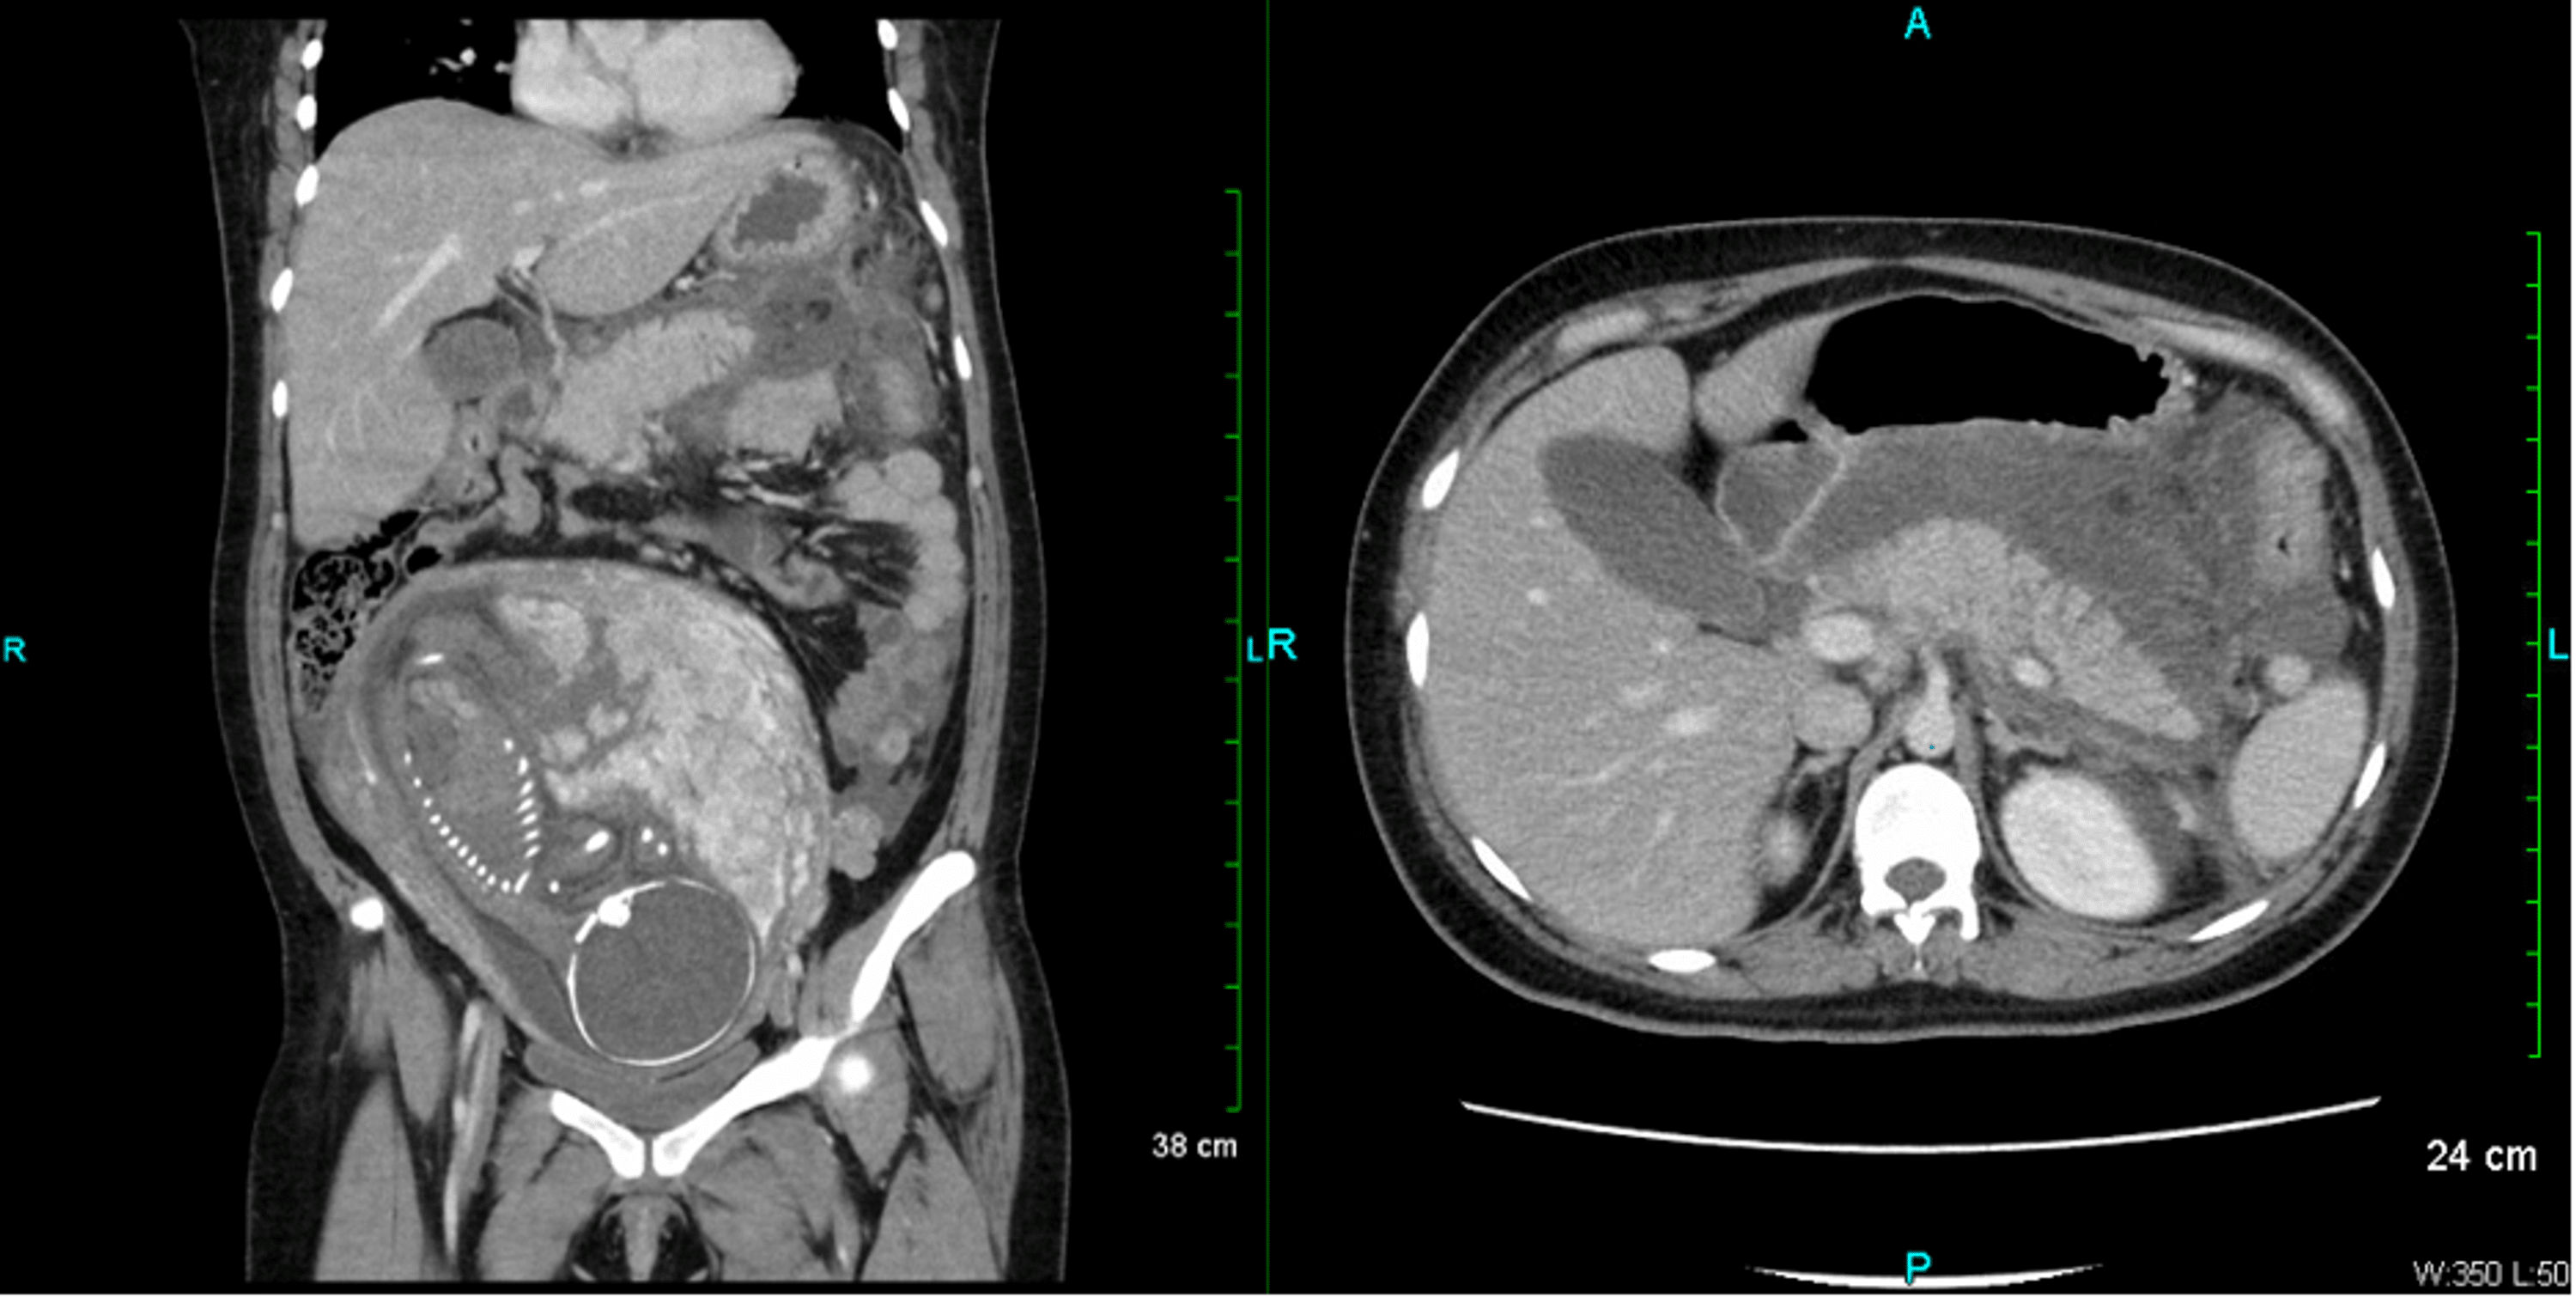

Figure 1 from Acute Pancreatitis In Pregnancy Semantic Scholar Pancreatitis During Pregnancy First Trimester The most common misdiagnosis of pancreatitis in the first trimester is hyperemesis. The incidence of acute pancreatitis during pregnancy is not different with respect to the general population, but this incidence. In women presenting with severe nausea and. Acute pancreatitis in pregnancy (apip) is a rare condition; Acute pancreatitis (ap) during pregnancy is a rare disease with an estimated incidence. Pancreatitis During Pregnancy First Trimester.

Figure 1 from Acute pancreatitis during pregnancy a case report Pancreatitis During Pregnancy First Trimester 19% of these were diagnosed in the first trimester, 26% in the. Acute pancreatitis in pregnancy (apip) is a rare condition; Acute pancreatitis (ap) during pregnancy is a rare disease with an estimated incidence rate of about 1 case per 1000 to 10. In this study, patients who developed pancreatitis in the first trimester had the lowest percentage probability to. Pancreatitis During Pregnancy First Trimester.

Figure 1 from Acute Pancreatitis during Pregnancy and Pancreas Pancreatitis During Pregnancy First Trimester In this study, patients who developed pancreatitis in the first trimester had the lowest percentage probability to reach term pregnancy. 19% of these were diagnosed in the first trimester, 26% in the. In women presenting with severe nausea and. In another study 43 pregnant women out of 147 197 were diagnosed with ap; The most common misdiagnosis of pancreatitis in. Pancreatitis During Pregnancy First Trimester.